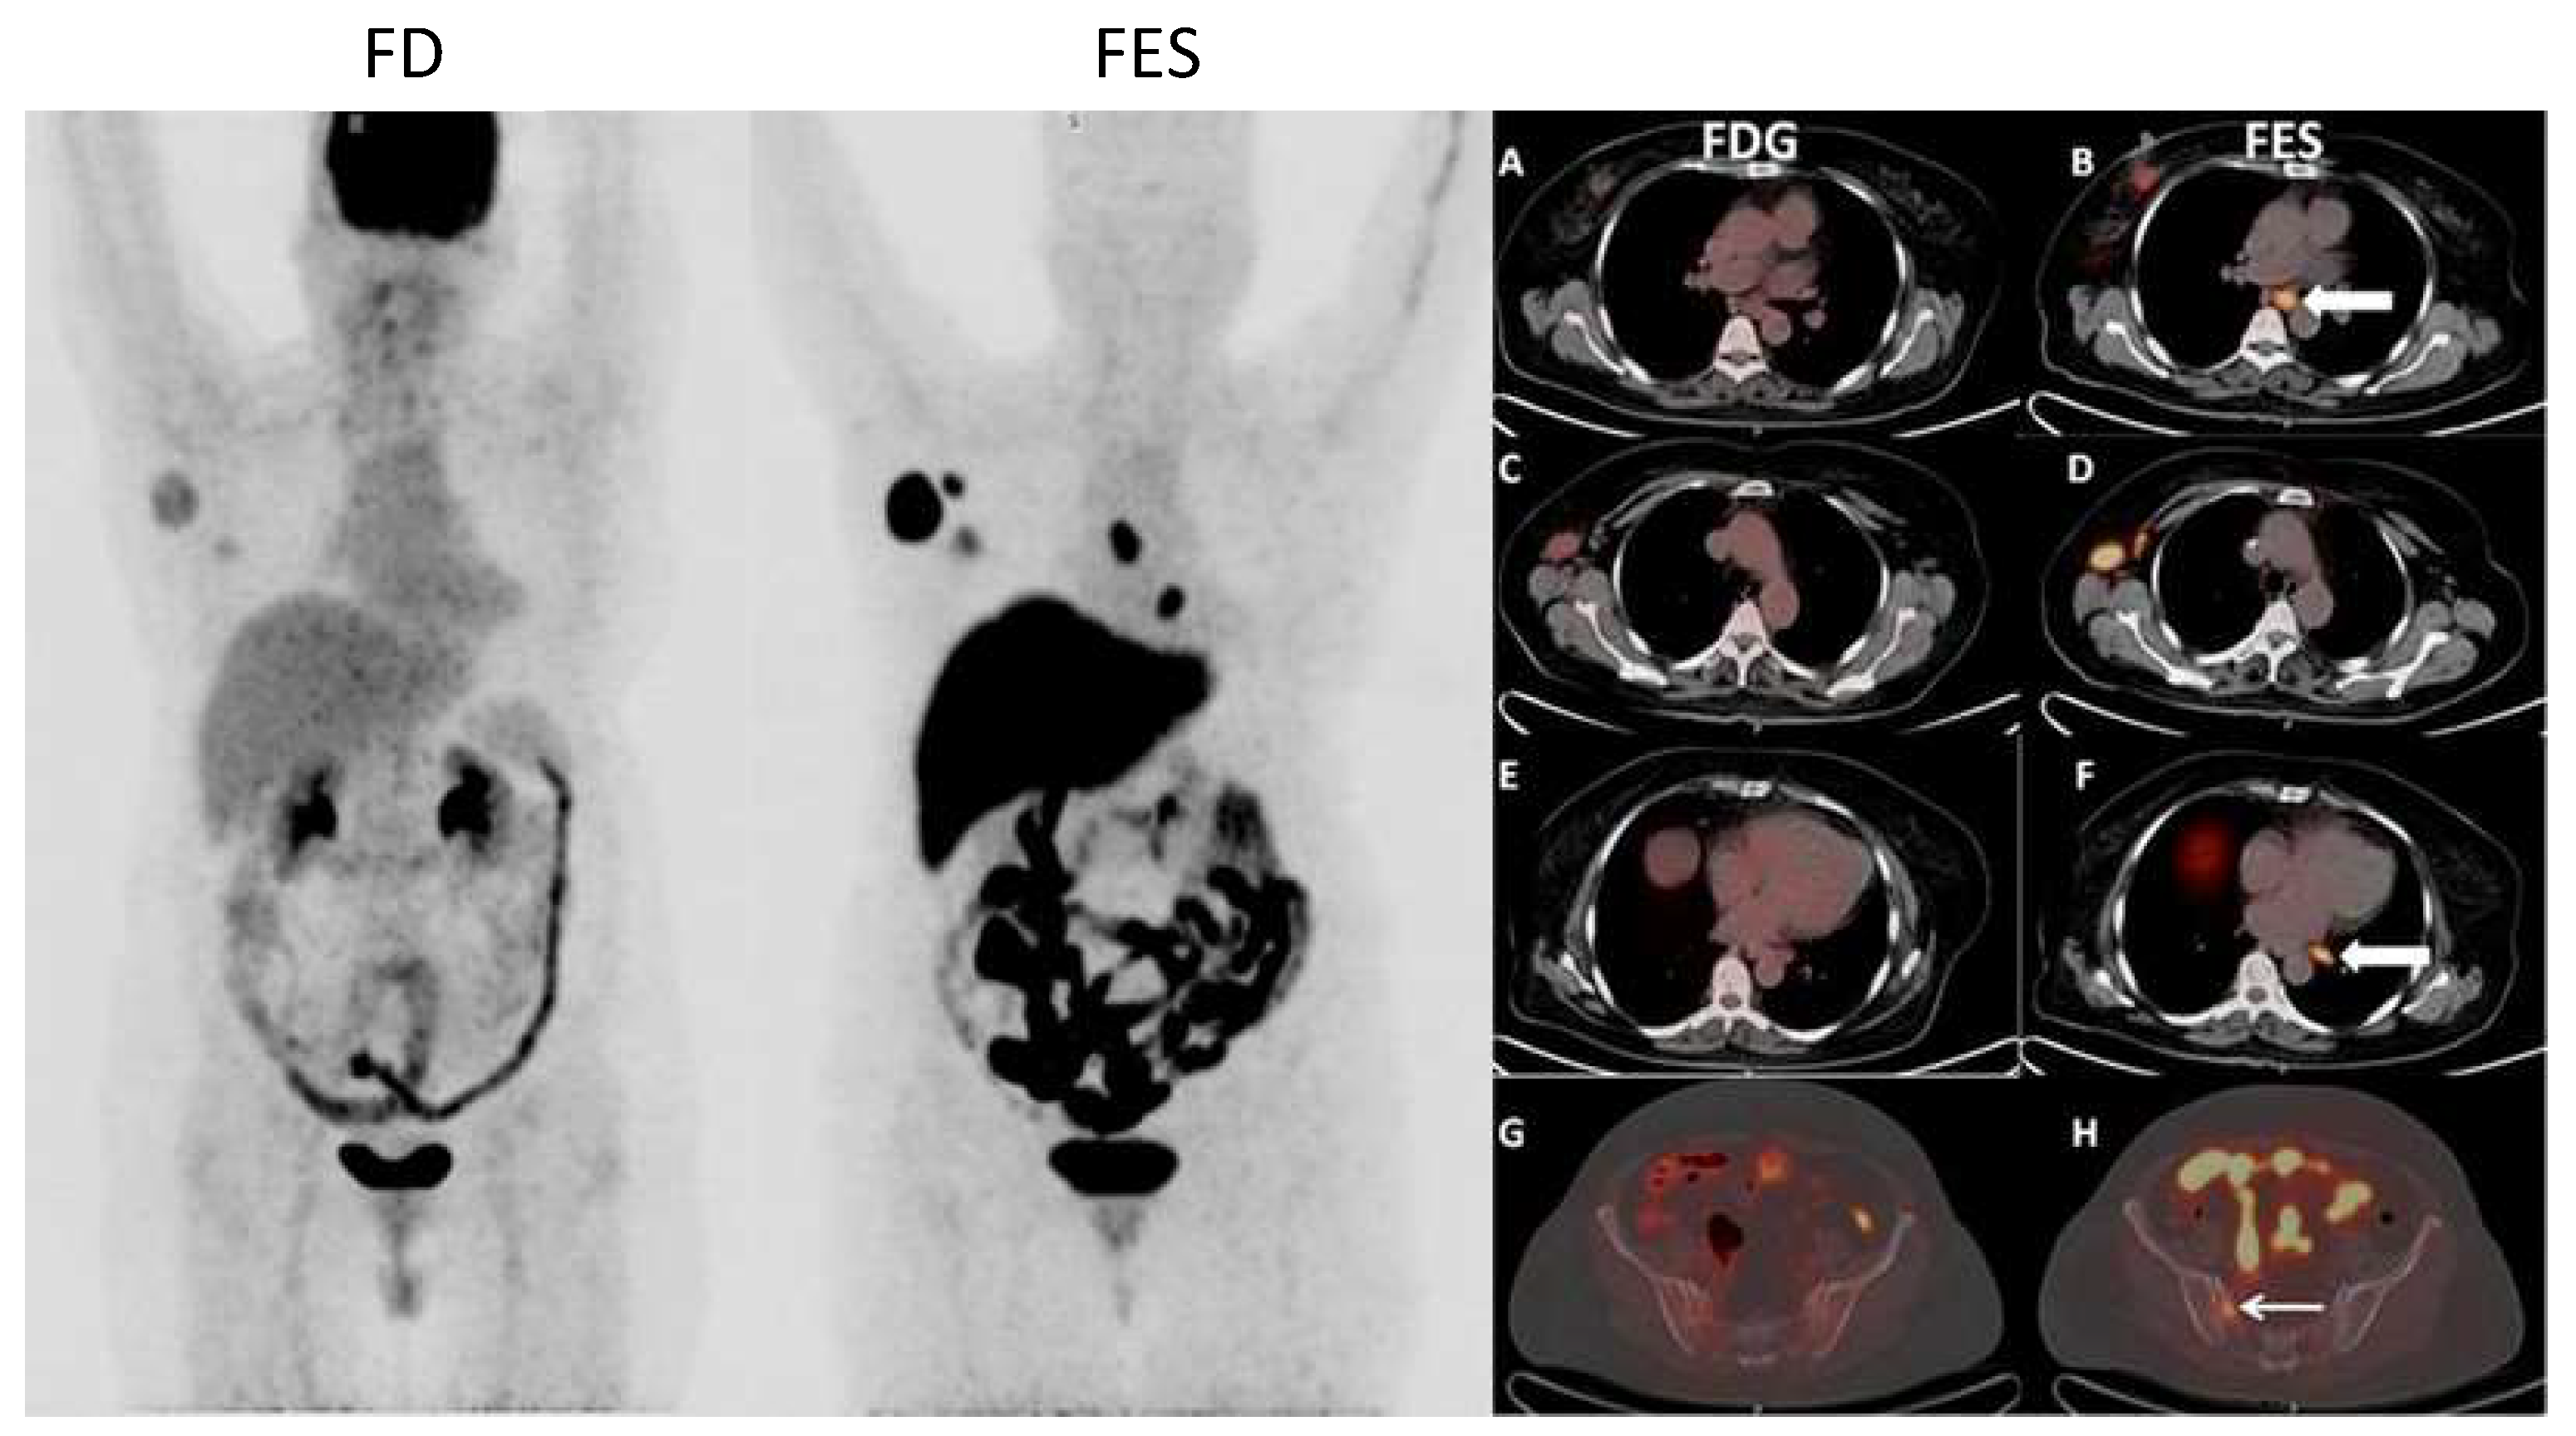

Figure 1 and Figure 2 show examples of 18F-FDG PET/CT imaging of breast cancer, with the former showing a case of locoregional malignancy and the latter showing a case of metastatic malignancy.

Figure 6 and Figure 7 show examples of images of breast cancer obtained using FES PET/CT.

Figure 1. 18F-fluorodeoxyglucose (18F-FDG) positron emission tomography/computed tomography (PET/CT) images of a 37-year-old woman with invasive ductal carcinoma of the right breast, showing an FDG-avid lesion in the right breast in keeping with the primary malignancy (a, b), as well as an FDG-avid right axillary lymph node which is likely metastatic (a, c).